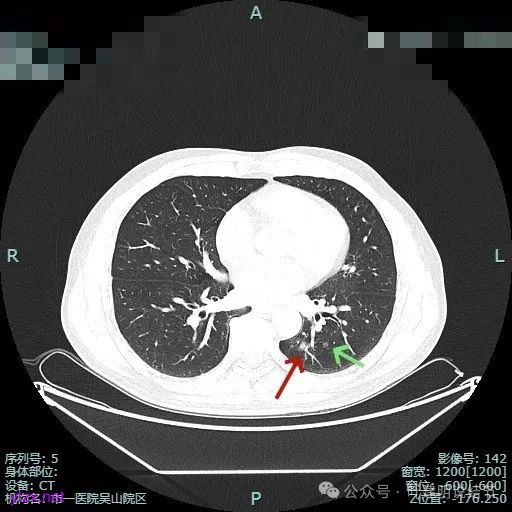

主病灶位于下叶后基底段下肺静脉水平,次病灶在同一层面位靠外基底段交界附近。

薄层上看主病灶不纯,有实性成分,也有血管穿行;次病灶是纯磨,微小的结节,但轮廓与边界较为清楚。

主病灶有血管进展与异常增粗,灶内有实性成分,中间有小空泡征。

主病灶混合密度,血管进入;次病灶小且淡,但轮廓清。